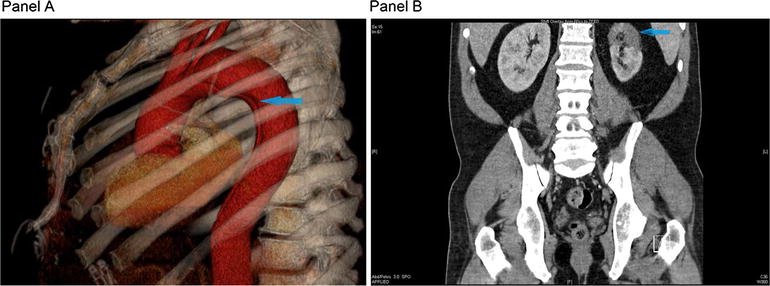

CT angiogram. There is a type B aortic dissection (Panel A, blue arrows) extending from just below the left subclavian artery to the proximal iliac arteries. The left main renal artery arises from the false lumen. A supernumerary left renal artery arises from the true lumen of the aorta and supplies a segment of that kidney (Panel B, blue arrow). The right renal artery is supplied by the true lumen, which is compressed by the false lumen at the site of the right renal artery takeoff